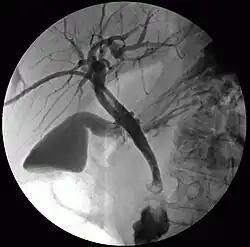

Percutaneous transhepatic cholangiography, percutaneous hepatic cholangiogram (PTHC) is a radiological technique used to visualize the anatomy of the biliary tract.[1] A contrast medium is injected into a bile duct in the liver, after which X-rays are taken. It allows access to the biliary tree in cases where endoscopic retrograde cholangiopancreatography has been unsuccessful. Initially reported in 1937, the procedure became popular in 1952.[2][3]